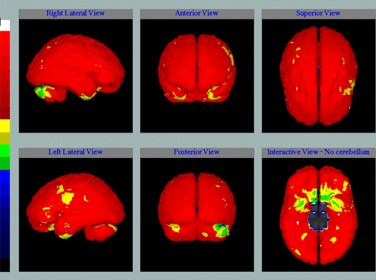

Однофотонная Эмиссионная Компьютерная Томография (ОФЭКТ)

Этот современный метод функциональной нейровизуализации отличается высоким уровнем информативности при диагностике целого ряда неврологических заболеваний. В случае атеросклероза сонной артерии благодаря трехмерному изображению метаболического статуса тканей и перфузии можно установить, насколько нарушено кровоснабжение головного мозга. Полученные данные позволяют дополнить информацию о структурно-морфологических изменениях в тканях, полученную методами КТ и/или МРТ

Карта ОФЭКТ у пациента, перенесшего инсульт

(желтым и зеленым цветами обозначены участки мозга, которые не получают кровь в полном объеме из-за сужения внутренней сонной артерии)

Карта ОФЭКТ у этого же пациента, спустя 6 месяцев после стентирования суженной внутренней сонной артерии.